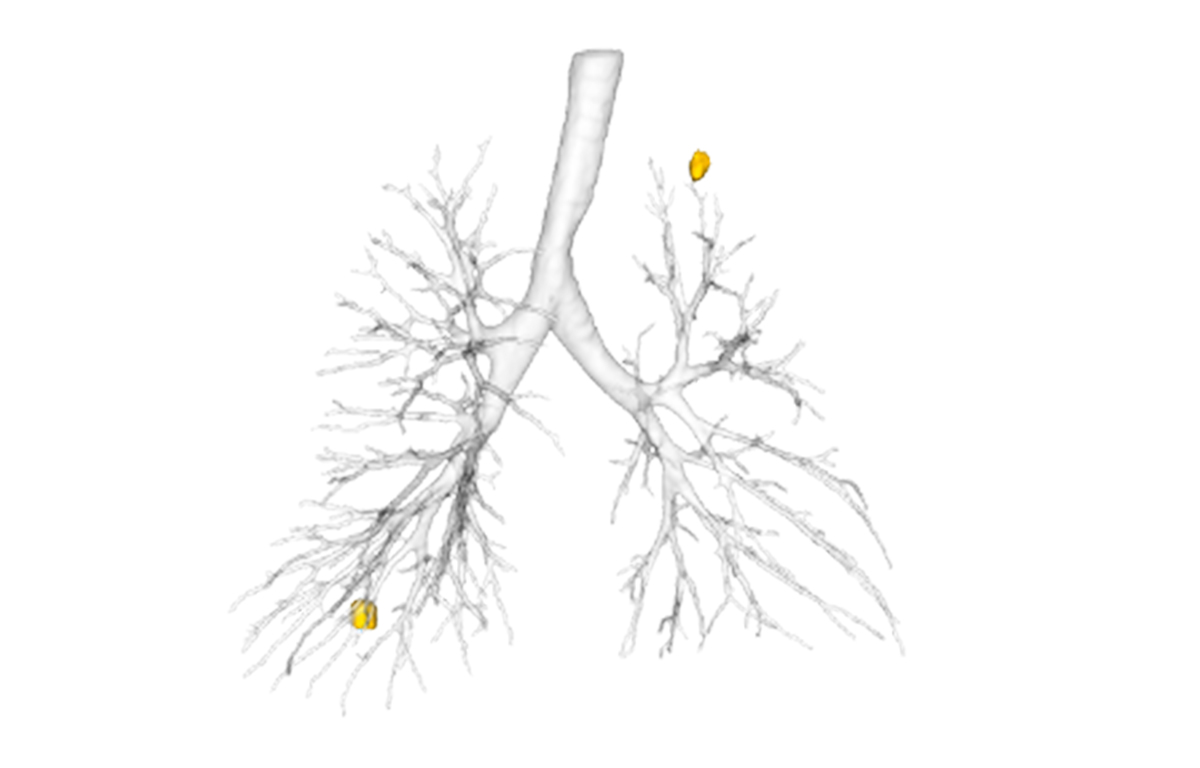

Built on advanced capabilities in lung segmentation and quantification, our AI technology interprets thoracic CT data with anatomical precision - capturing airway trees, parenchymal patterns, and vascular structures, even in severely diseased lungs.

Examples of core capabilities that provide complementary detailed, procedure-relevant insights include:

- Segmentation of anatomical structures up to sub-segmental level

- Quantitative analysis of complex lung patterns and diseased regions

- Anatomical mapping to support navigation planning and guidance